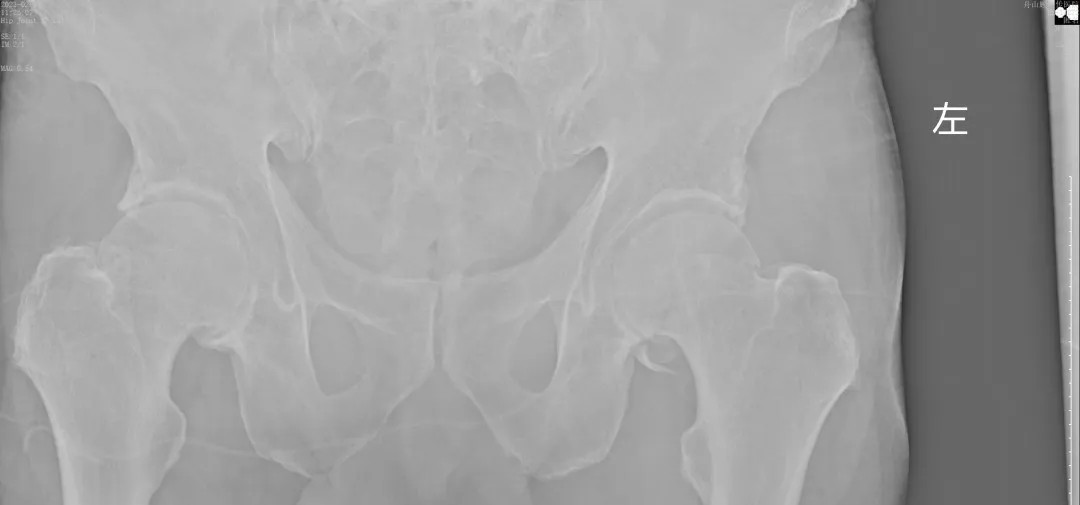

經(jīng)過王副主任認真仔細的檢查,并結(jié)合X線攝片后,他告訴患者及其家屬:“周大爺是外傷導(dǎo)致的急性髖關(guān)節(jié)脫位、髖臼骨折!”一聽脫位骨折了,患者及家屬焦慮萬分,擔(dān)心手術(shù)給身體和經(jīng)濟帶來的巨大壓力。王副主任耐心告知周大爺一家人:“周大爺這種病情可以保守治療,用我們顧氏的正骨手法可以復(fù)位的,不需要開刀,價格也實惠”。家屬聽到不用做手術(shù),瞬間放心不少,表示非常愿意配合治療。

(術(shù)后復(fù)片  關(guān)節(jié)對位良好)